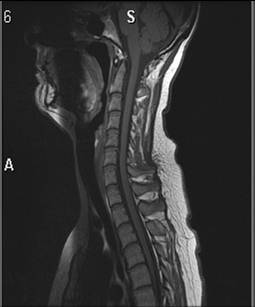

Columna cervicalis, normal, MR

MR af normal hals med to forskellige vægtninger så væsken i rygmarvshulen bliver henholdsvis sort (T1-vægtet) og hvid (T2-vægtet).

På dette billede er væsken i rygmarvshulen sort (T1-vægtet).